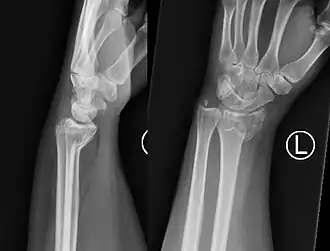

![]() Fractura de Smith muñeca izquierda | ||

La fractura de Goyrand-Smith o fractura de Smith (o fractura de Colles invertida) es una fractura del extremo distal del radio con desplazamiento palmar del fragmento y la mano, respecto del radio; esto produce la deformidad en pala de jardinería. Su epónimo se debe al médico, cirujano y político francés Gaspard Goyrand[1] y al cirujano ortopédico irlandés Robert William Smith que la describe en su obra Treatise on Fractures in the Vicinity of Joints, and on certain forms of Accidents and Congenital Dislocations, publicada en 1847.[2]

El fragmento de fractura distal se desplaza de forma volar (ventralmente), a diferencia de la fractura de Colles, que el fragmento se desplaza dorsalmente. Dependiendo de la gravedad del impacto, puede haber uno o varios fragmentos y puede o no afectar la superficie articular de la articulación de la muñeca.

El diagnóstico inicial es clínico mediante al exploración, haciendonos sospechar la presencia de este tipo de fractura si se presentan los signos detallados arriba. Ante esta sospecha, el diagnóstico final apropiado de este tipo de fracturas necesita la realización de una radiografía simple del antebrazo distal y del carpo en al menos dos proyecciones: antero-posterior y lateral. En algunos casos, una vez realizada la radiografía simple, cuando las imágenes muestren que se trata de una fractura multifragmentario o compleja, la realización de una tomografía computarizada simple de la lesión puede ser útil para guiar el tratamiento.